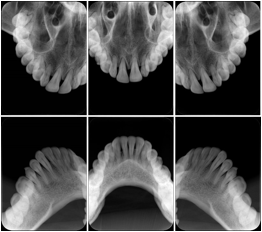

2. A patient requests cosmetic surgery to enhance their facial appearance. The case requires consultation between an orthodontist in New York and an oral surgeon in California. The cephalometric series of 2D projections constructed from the volumetric CT data that is used for the discussion is arranged by a Structured Display for transfer between the two practitioners.

Cephalometric Series Structured Display

Figure OO-2. Cephalometric Series Structured Display